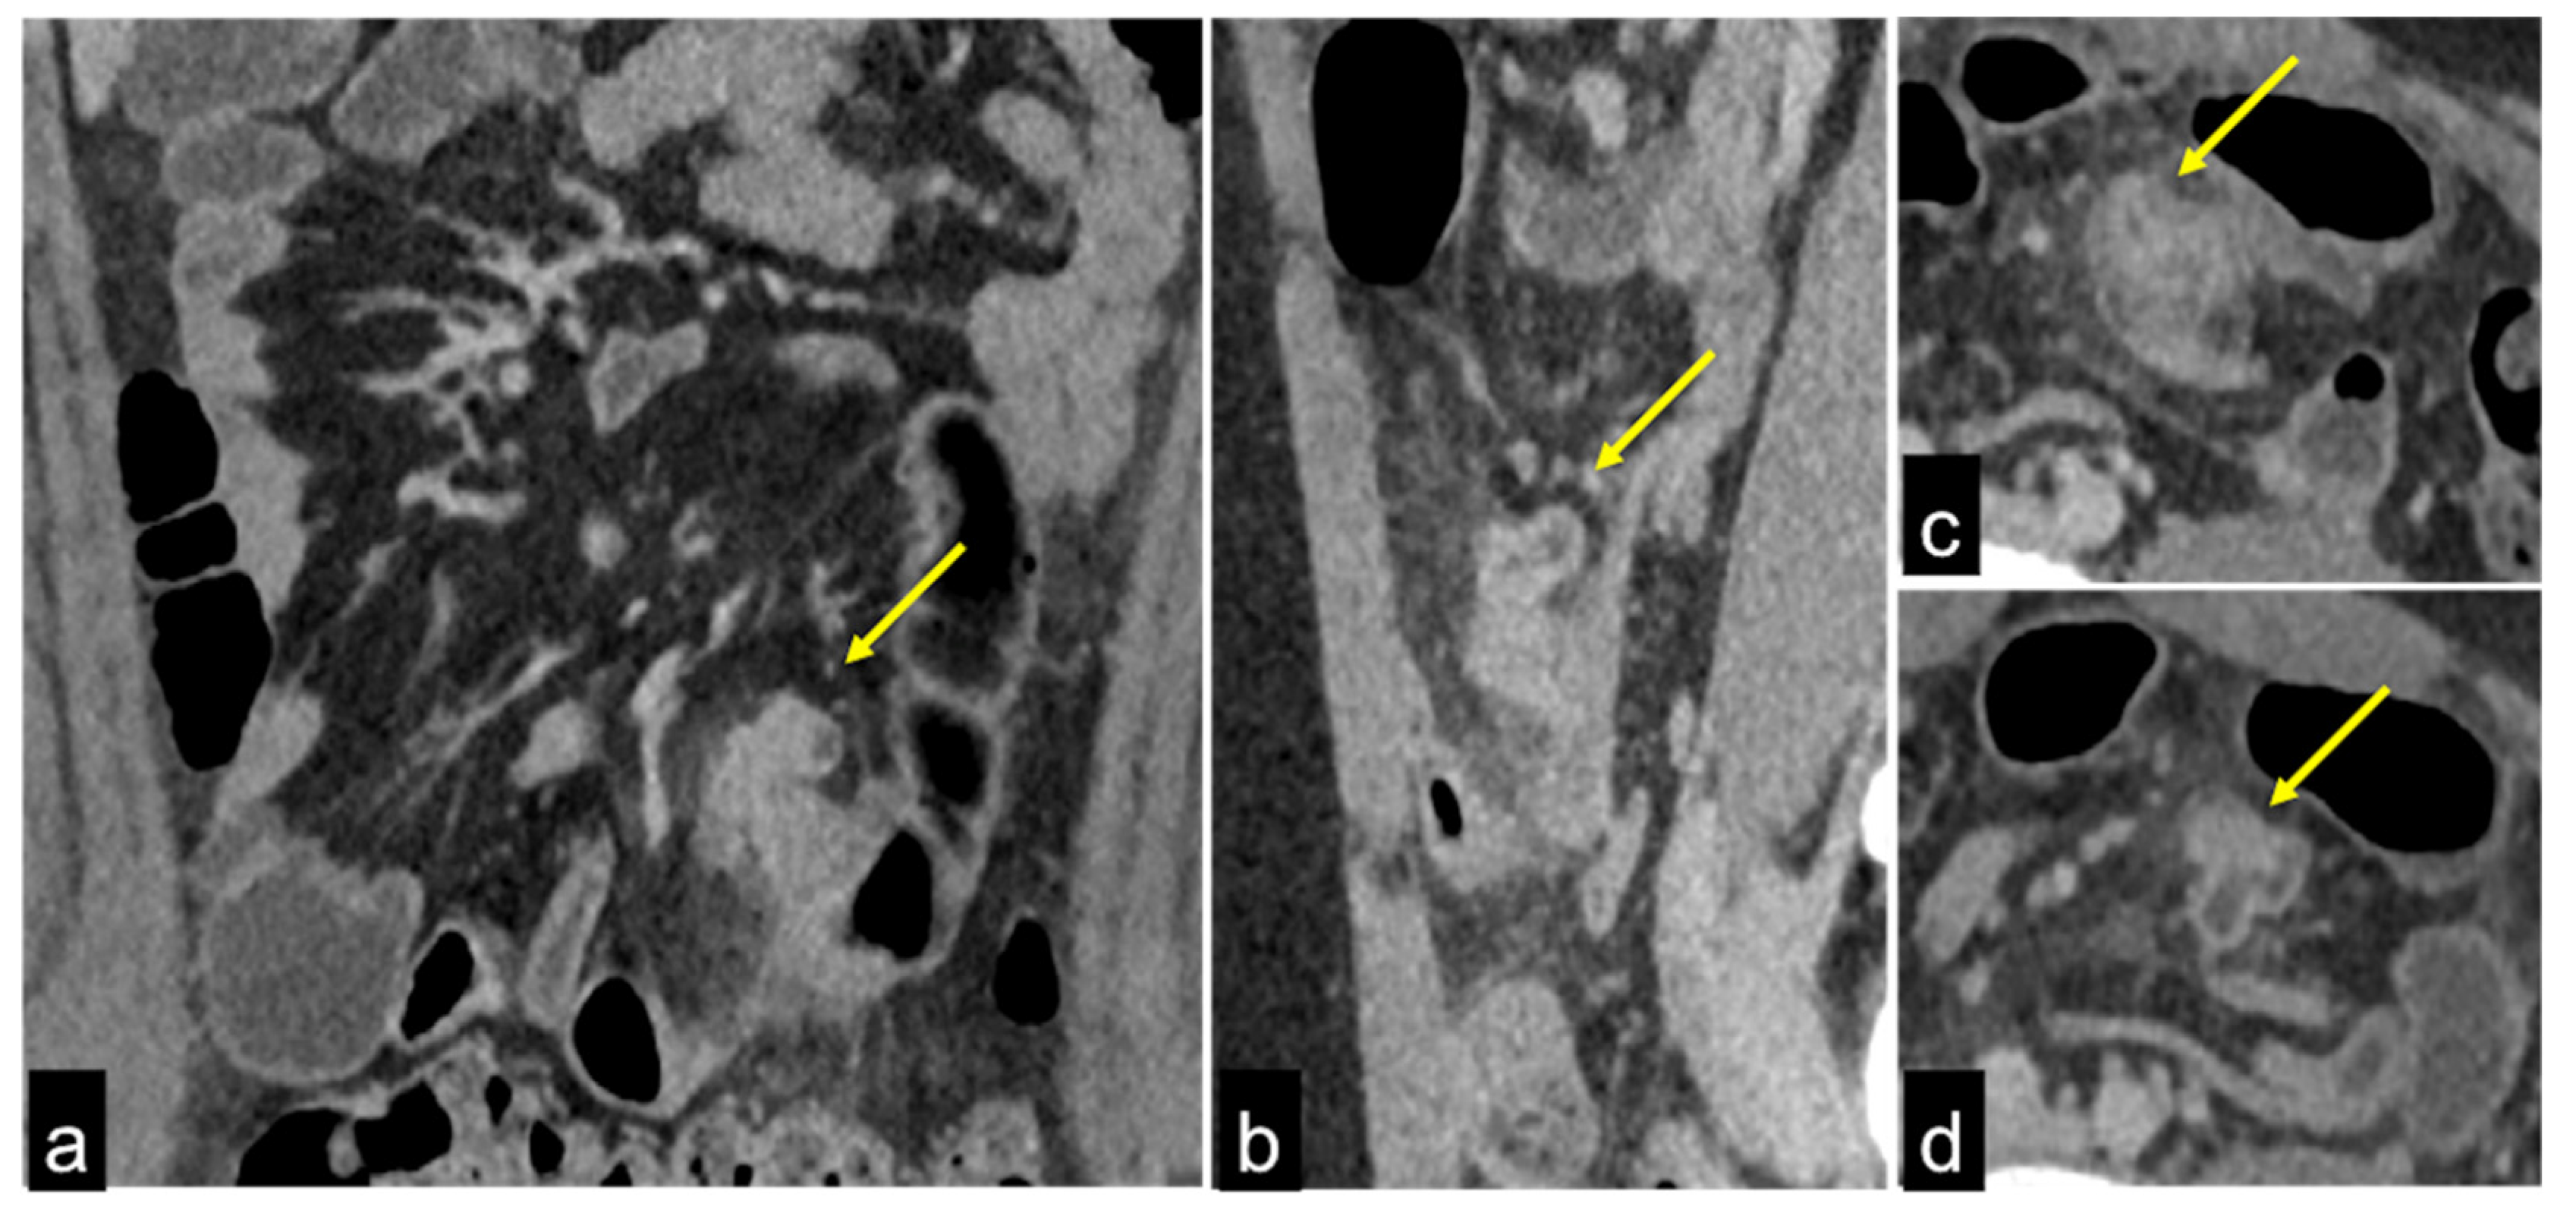

| Meckel’s Diverticulum (Figure 30) | Asymptomatic or, rarely, massive gastrointestinal bleeding. | A diverticulum with fluid or air content originating from the antimesenteric side of the distal ileum. |

| Aorto-Enteric Fistula (Figure 31) | Bleeding in a patient with a history of surgery for aortic aneurysm. | A connection between the aorta and the intestinal lumen. Absence of adipose cleavage planes. |